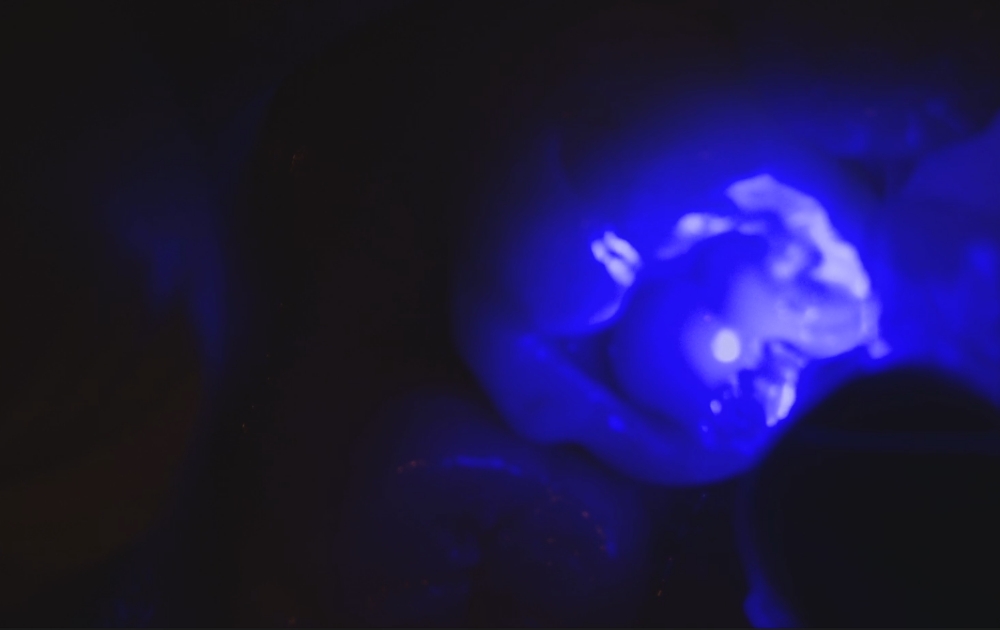

• 8.充填したプラスチックに光を当てて硬化させます。専用の光照射器で固め、強度を持たせます。

8.充填したプラスチックに光を当てて硬化させます。

専用の光照射器で固め、強度を持たせます。